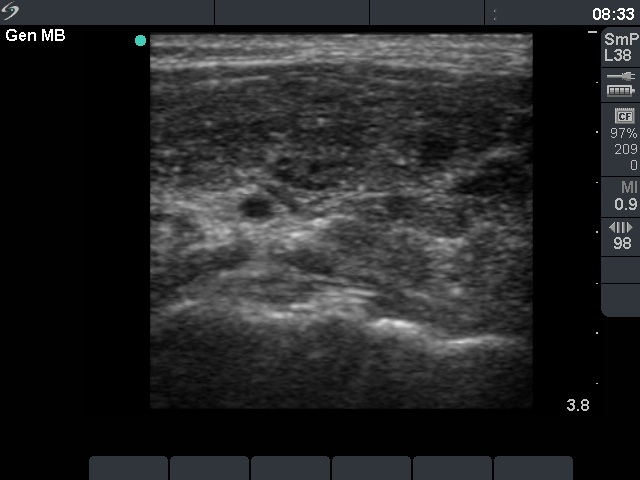

Follow-up examination 4 weeks after surgery (fourth and fifth rows):

Radioiodine treatment was planned. The patient visited us to get information about the prognosis of her disease.

Palpation: no abnormality.

Ultrasonography: There was no parenchyma in the thyroid beds. There were multiple enlarged lymph nodes in the lateral side of the neck. One of them very close to the thyroid seemed to be benign, reactive, but there was a chain of atypical, suspicious lymph nodes next to the strernocleidomastoid muscle.

Cytology: papillary cancer.

The patient was reoperated. Histopathology disclosed metastatic foci in the lymph nodes. 6 weeks later she underwent radio-iodine treatment.

3. The performance of ultrasound may have role after surgery (thyroidectomy and appropriate lymphadenectomy) but before radioiodine treatment. Ultrasound examination can reveal insufficiency of surgery in around 10 to 20% of such cases. Most of these cases occur when either the surgeon performed the exploration is relatively inexperienced or in cases where the diagnosis has not been made preoperatively and therefore the appropriate lymphadenectomy was not performed.